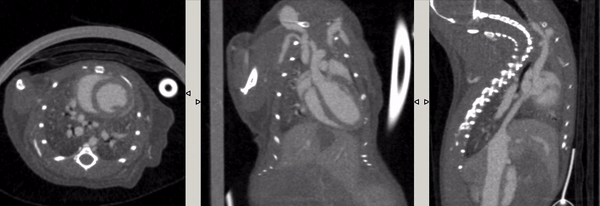

ECG gating: live mice were injected with the development enhancer Exitron 12000, with ultra-high temporal resolution (10ms), and the imaging time was 2min40s.

6、Contrast-enhanced tumor CT imaging

Tumor study: Contra-enhanced CT was used to examine liver tumors in living mice: Exitron 12000 was injected, FDK was reconstructed, and the imaging time was 4min, 100µm voxel size.